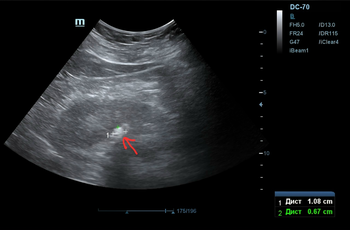

Делаем УЗИ почек (фото 3 — 5) — по центру левой почки подозрение на твёрдый камень, будто состоящий ~ из трёх слившихся фрагментов.

Фото 3 — УЗИ почки